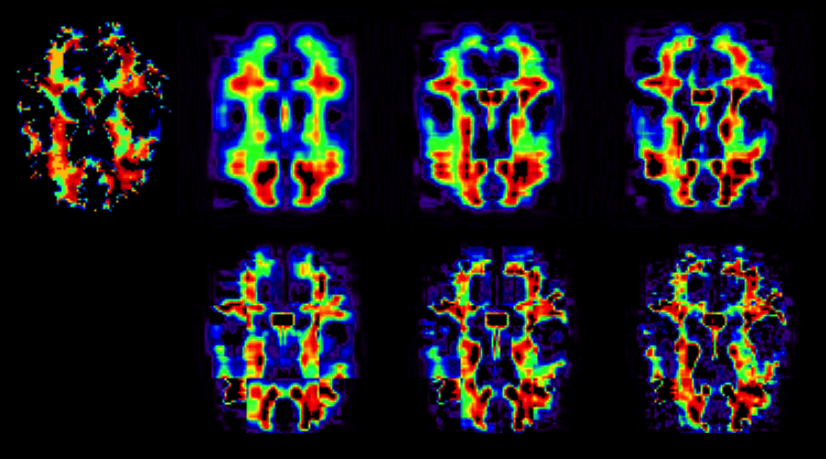

We consider the non-partition model and compare the Bayesian method with the standard alternating least squares method (Kolda and Bader,, 2009). Figure 7 shows an axial slice of the original white Matter RAVENS map and the reconstructed images for ranks R=5,10,𝑅510R=5,10, and 202020 as S=1𝑆1S=1. Table 3 presents RMSEs obtained from the three methods in all scenarios. The Bayesian decomposition method gives a smaller RMSE for all cases. As expected, the higher the rank, the smaller the reconstruction error.

Refer to caption

Figure 7: Bayesian tensor decomposition results. Top panels: the image on the left represents an axial slice of the RAVENS map image, followed by reconstruction results for the non-partition model. Bottom panels: reconstruction results for the partition model. From left to right, we have the decomposed images for ranks R=5,10,𝑅510R=5,10, and 202020, respectively.